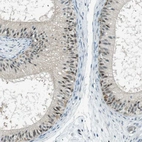

Immunohistochemical staining of human epididymis shows moderate cytoplasmic and nuclear positivity in glandular cells.